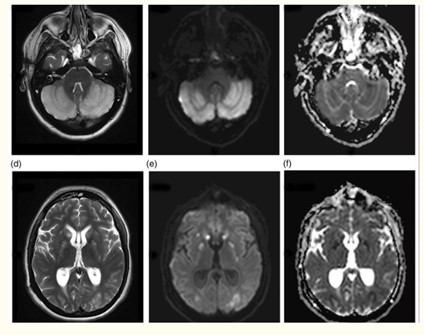

En esta investigación que se viene señalando, se puede mencionar el caso de un joven de 16 años, con alteración aguda del estado mental por inhalación de vapor de heroína. Se le efectuó una RM que evidenció hiperintensidades en T2 de la sustancia blanca simétrica difusa infratentorial y supratentorial. El diagnóstico clínico en este caso fue rabdomiólisis, que afecta predominantemente la musculatura posterior del cuello(21) (ver Imágenes 11 y 12).

Otro caso que merece ser comentado es el de un adolescente de 15 años que presentó encefalopatía y signos extrapiramidales por ingestión de metadona. La RM evidenció focos de infartos agudos en el caudado y putamen, así como infartos corticales de la línea divisoria de aguas parietales(21) (ver Imagen 13).

En el caso que se viene ilustrando, la RM mostró T2 difuso con hiperintensidades en el cuerpo calloso bilateral frontal y parietal, así como lesión difusa de la sustancia blanca del cerebelo. Se localizaron áreas de difusión restringida en los ganglios basales bilaterales, lo cual tenía relación con la pérdida neuronal mediada por estrés oxidativo (ver Imágenes 15 y 16). El tratamiento permitió la recuperación progresiva del habla y la orientación de la persona. (23)